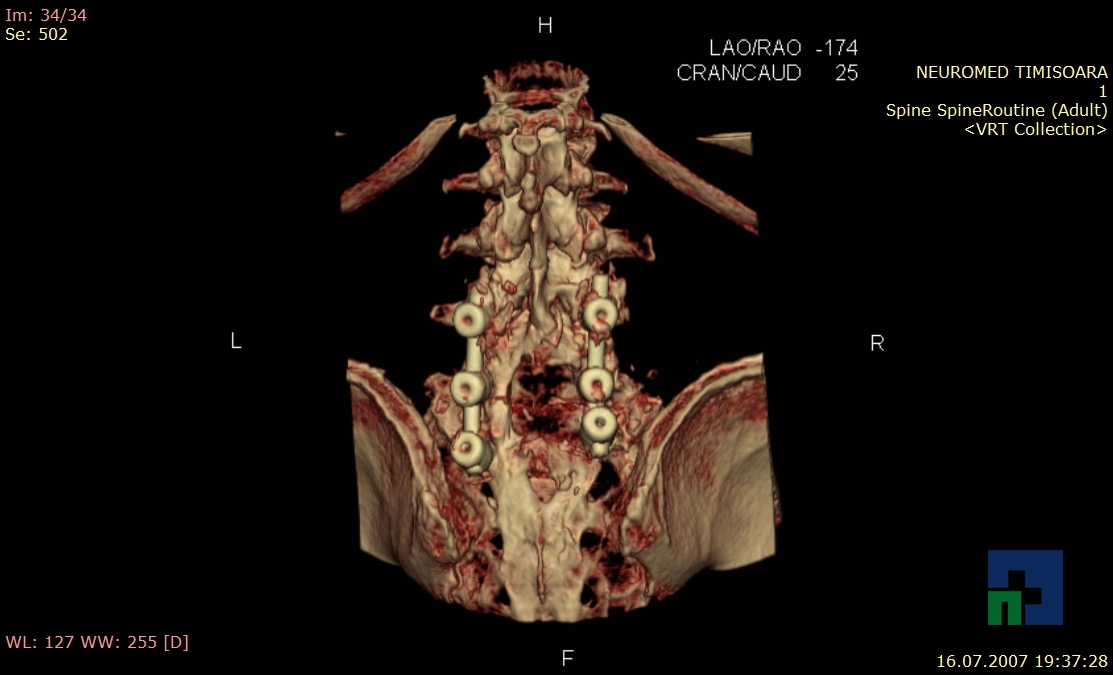

- Diagnosticul fracturilor:

- Unice

- Multiple

- Cu înfundare